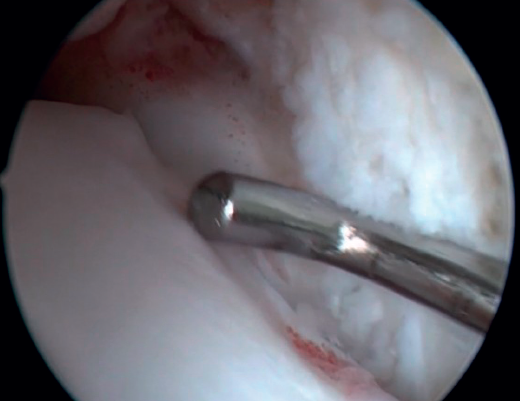

Bassett's ligament should be preserved as long as it does not have a pathological appearance, ruling out thickening, partial tears or reciprocal lesions on the anterolateral surface of the talus (Figure 6), which are associated with anterolateral or rotational instabilities. The peroneal insertion is used as a reference to locate the distal insertion of the ATFL. The deltoid ligament at the medial groove should be inspected if associated rotational instability is suspected. During arthroscopy, direct ligament repair can be performed using sutures and anchors.